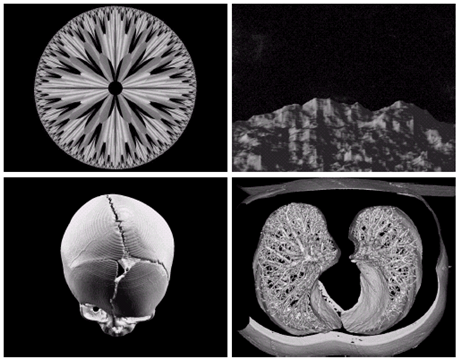

• 전자현미경: SEM(scanning electron microscope)

• 전자빔을 쏘아 각 위치에서 빔과 샘플과의 상호작용을 기록

Image

텅스텐필라멘트의 250x SEM영상, 손상된 IC의 250x SEM영상

• 초음파: 1~5MHz 이하. 의료진단

a)아기1 b)아기2 c)갑상선 d)손상된근육